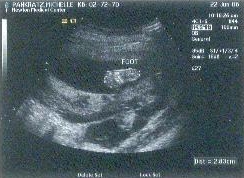

Leo's foot is also clearly visible in the picture below. The sonographer was a very strange lady.